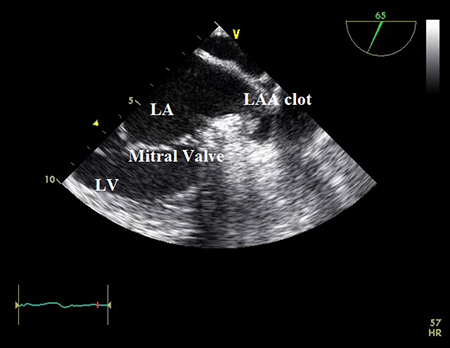

Transesophageal echocardiogram showing left atrial appendage clot. LA=left atrium; LAA=left atrial appendage; LV=left ventricle

From the collection of Dr Bharat Kantharia